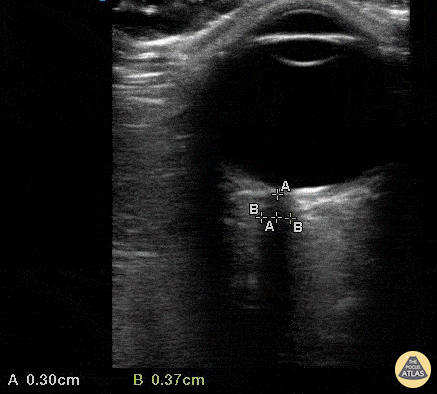

Orbital - Normal ONSD

A 35 yo female presented to a rural ED with worsening headache accompanied by nausea/vomiting after failed treatment for sinusitis. The department did not have immediate access to CT scanning, therefore Optic Nerve Sheath Diameter (ONSD) was used to assess for associated increased intracranial pressure. The optic nerve sheath is contiguous with the subarachnoid space, making ONSD an indirect measure of intracranial pressure. Visualize the hypoechoic optic nerve posterior to the globe and measure 3mm back from the globe (calipers A) to determine site of measurement . Then measure to the edges of the sheath (calipers B) horizontally. Value >5mm is concerning for increased ICP. This ONSD is normal. Mandy Peach, MD @mandy_peach Saint John Regional Hospital. NB, Canada